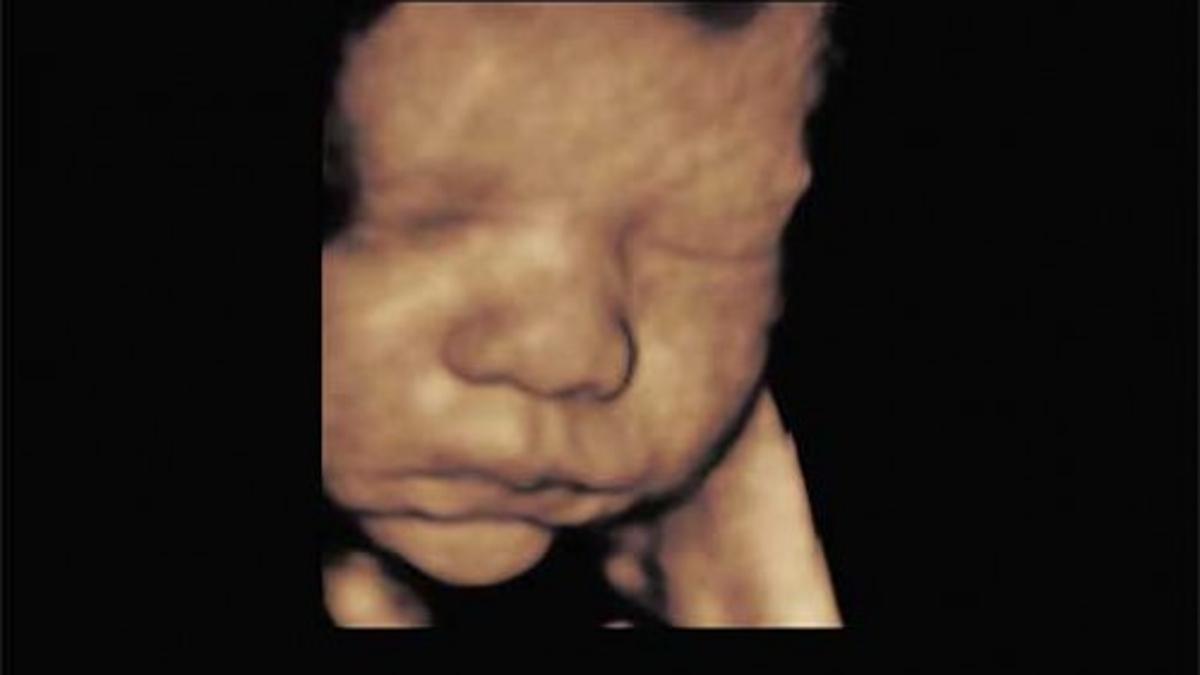

31 Week 3d Ultrasound Big Nose

So if you think your babys nose is extremely large based on the 3d scan dont be too alarmed.

If you happened to see your baby has a big nose that doesnt look like yours at all this is nothing to be worried about. For the most part seeing a baby with big nose on the ultrasound is nothing to worry about but sometimes it could be pointing to something else. A closer look inside your womb. Aside from that your babys face is literally being smushed up against your placenta.

See an unborn baby smile in the womb at just 31 weeks gestation with 3d4d ultrasound technology at goldenview ultrasound. Some ultrasounds even show an incredibly thick set of lips because that is whats being pushed against the uterine wall or placenta. This could happen in the womb but could also happen afterward. Generally it is better to address these injuries right away.

Her face definitely grew into her nose.